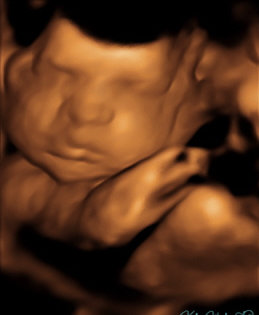

Our excitement and anticipation for Luna led us to document every stage she goes through. At 12 weeks you can see our angel was almost the size of a lime... Then, at 20 weeks, she grew into a good-sized fig. Upon arriving, our Luna will hopefully be the fully-grown Melon she’s meant to be! You can check out her journey here. We want everyone to be part of the amazing ride we are going through!